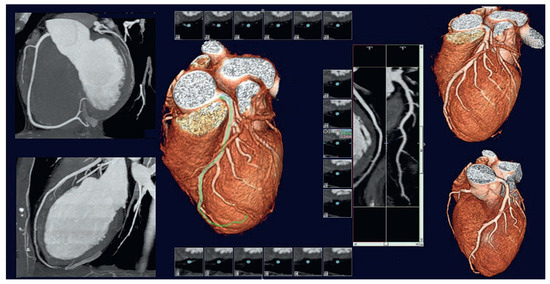

Coronary CT angiography (CTA) is emerging as a highly effective alternative imaging technique for the assessment of coronary artery disease (CAD). The rapid evolution of multidetector CT scanners has lead to major improvement in temporal resolution o...